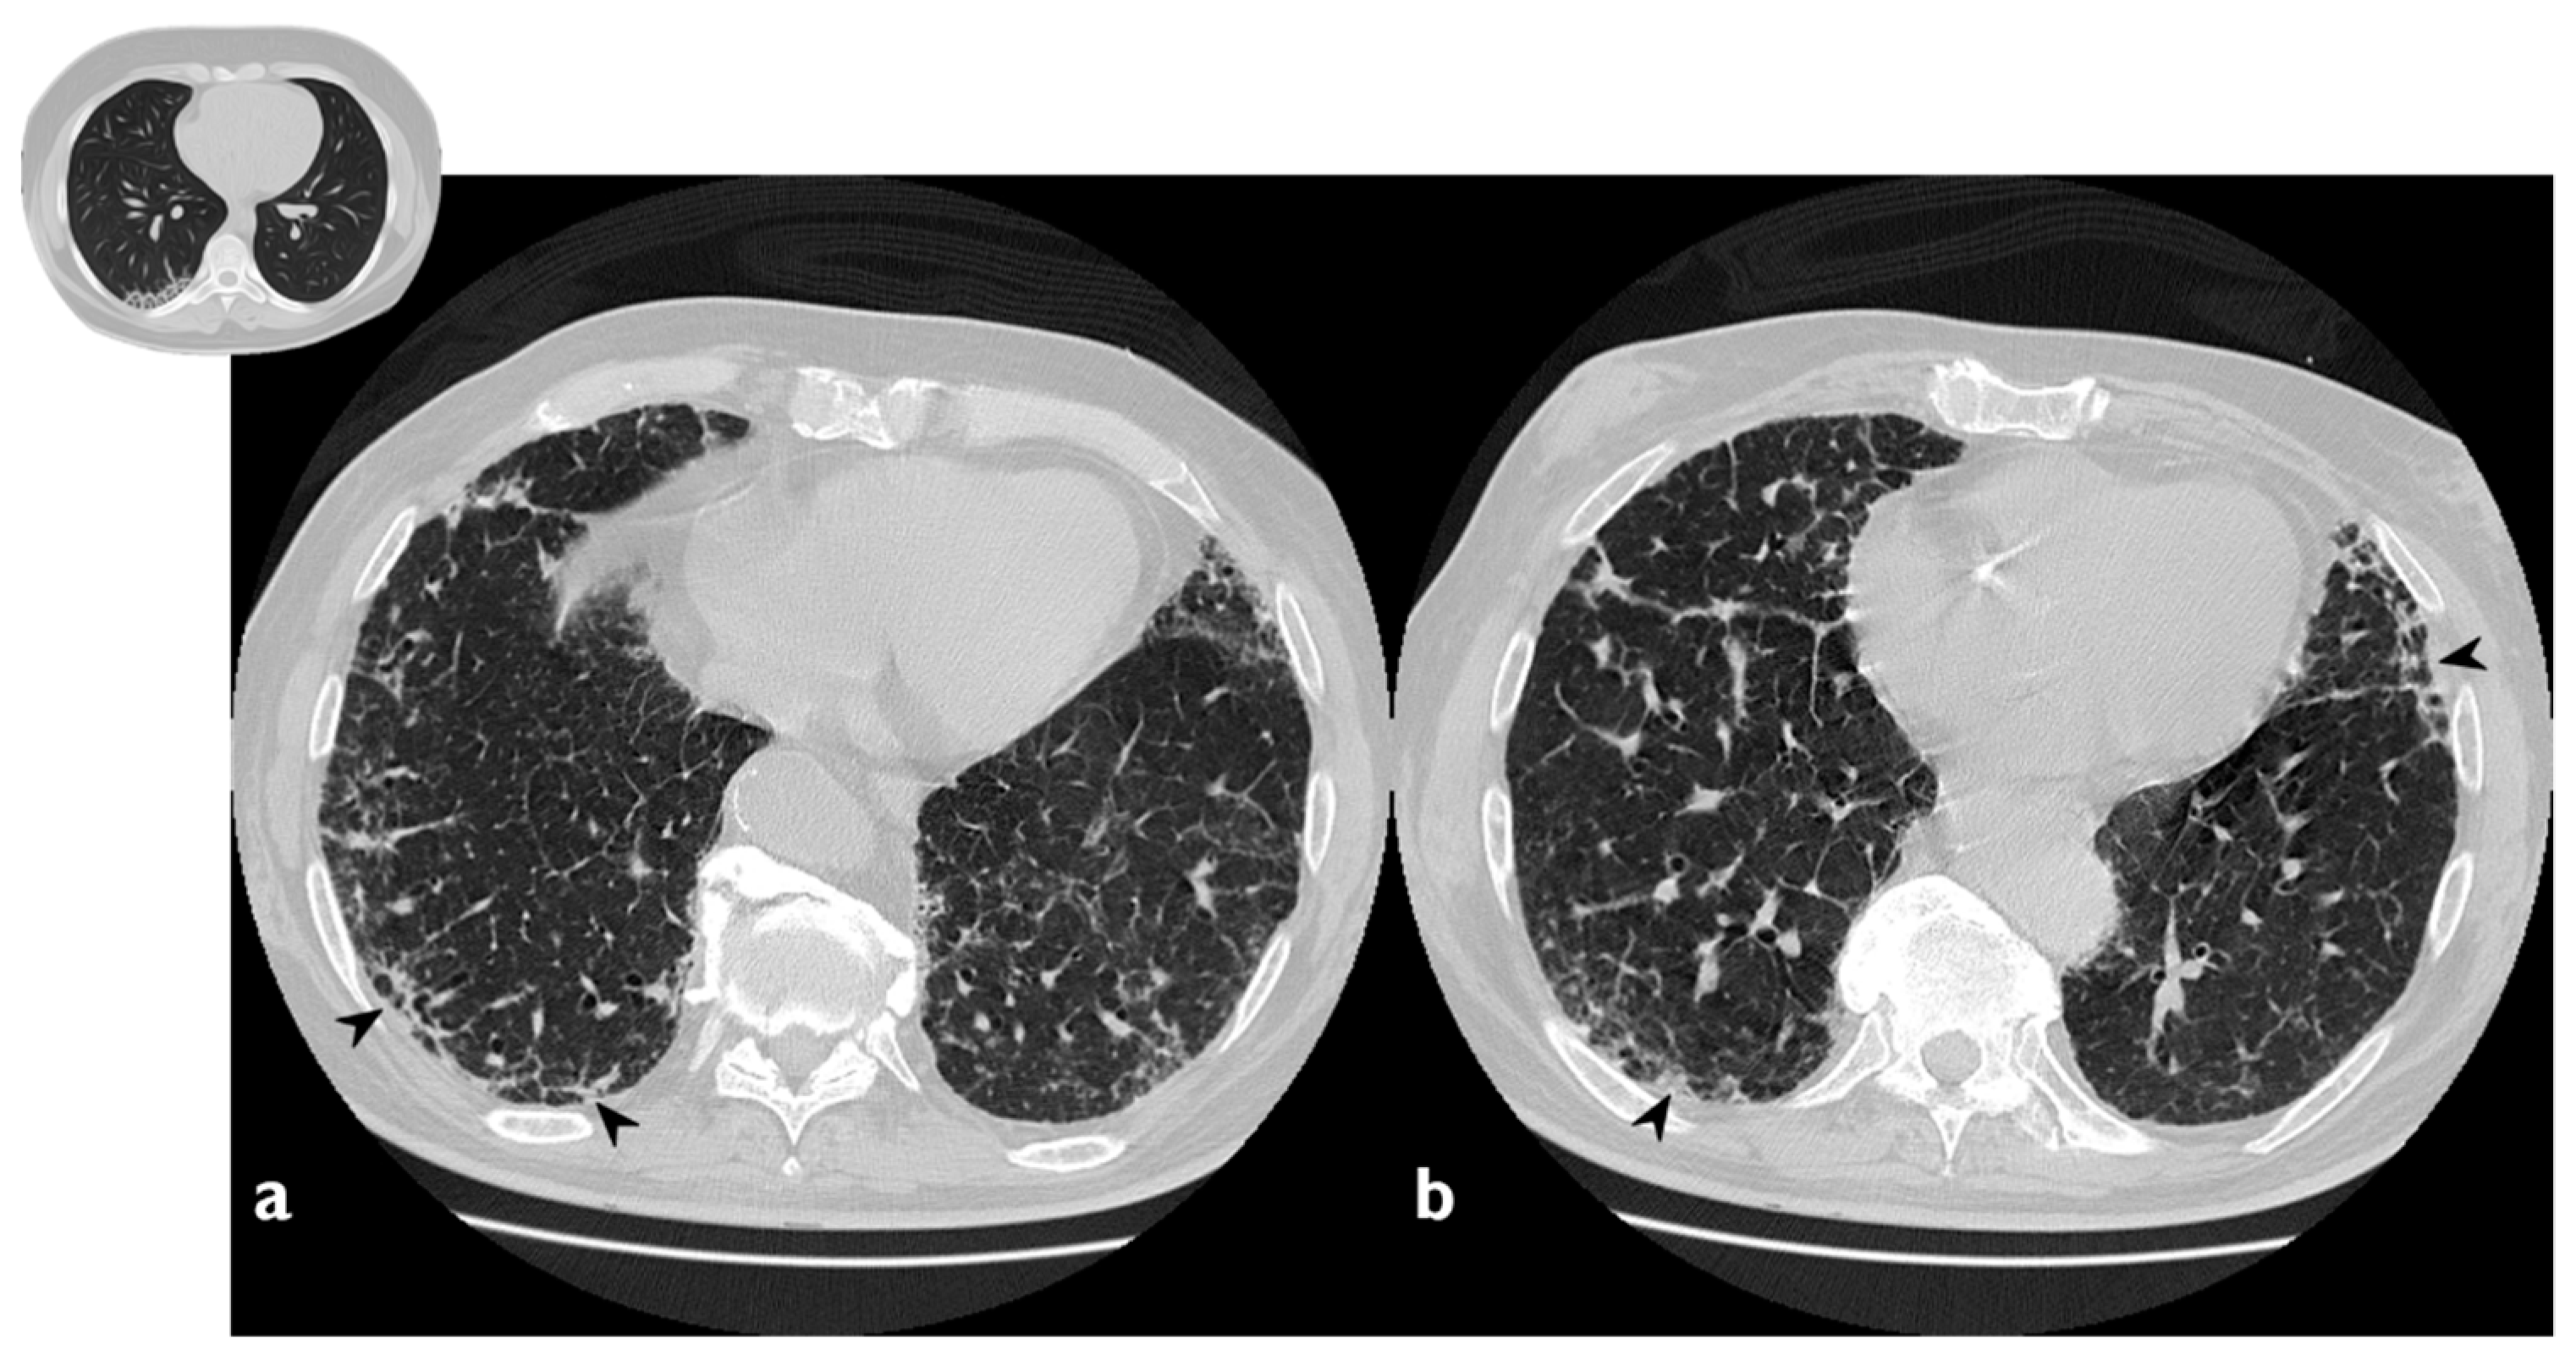

1.3.4. Progressive Fibrosis Pattern

OP can produce sub-pleural basal reticulations and architectural distortion in about a 15% of cases, mimicking the appearance of nonspecific interstitial pneumonia (NSIP); the reticulations coexist with regions of consolidation or appear later (Figure 5) [24]. This presentation seems to be associated with a poor outcome [26]. As reported by OIkonomou et al., this pattern may occasionally result in honeycombing and must be differentiated from usual interstitial pneumonia (UIP) [20]. Pathologically, alveolar epithelial damage is a common condition in both OP and UIP. In OP, the necrosis of alveolar epithelium is followed by the migration of fibroblasts from the interstitial compartment to airways, while, in UIP, fibroblastic foci are restricted to interstitium, and intraluminal fibrosis is less extensive than in OP [20].

Figure 5. Fibrotic pattern: bilateral sub-pleural reticulations (arrowheads) and architectural distortion, clearly visible in peripheral regions of right lung (a) and left lung (b).